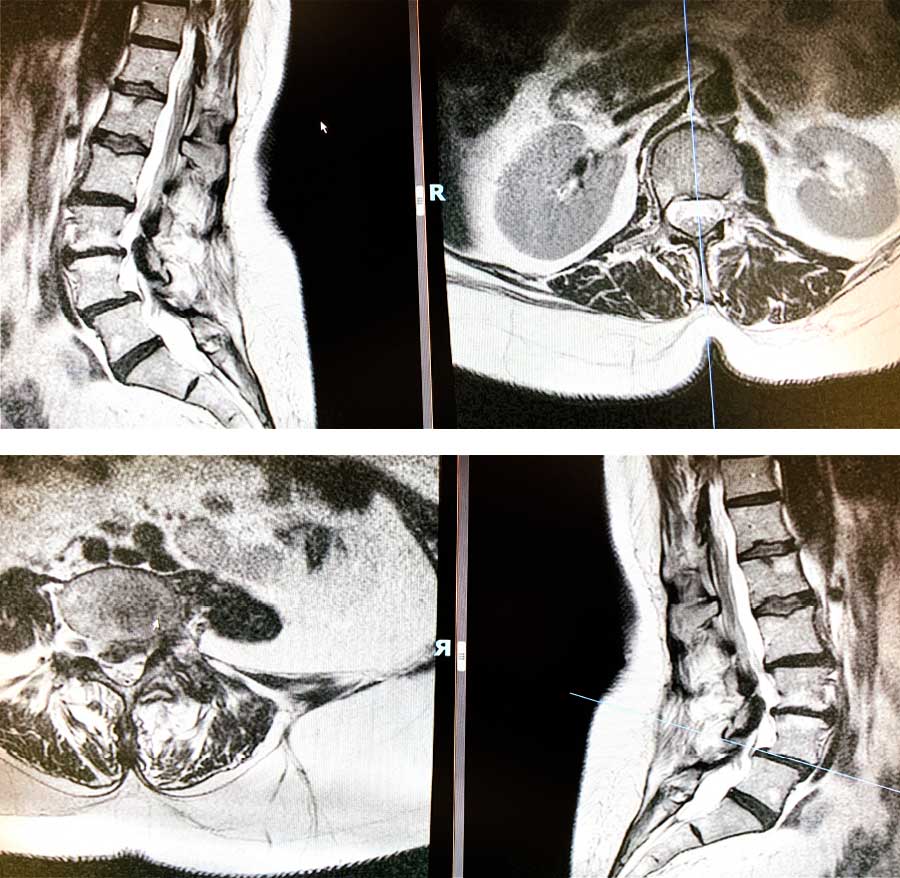

Estenosis de dos niveles: L4L5 listesis, L5S1 quiste

Tras conocer esta información, ya pudimos conocer el territorio donde teníamos que ir para buscar la patología. Tal y como hemos hecho en casos clínicos similares, le realizamos una resonancia y objetivamos que la raíz L5S1 tenía un quiste sinovial que comprimía dicha raíz.

Además, en las raíces L4 y L5 tenían una leve listesis. Esto significa que la vértebra cuarta, con respecto a la vértebra quinta está un poco desplazada y provoca en la paciente una pequeña hernia que le comprime la raíz L4 y probablemente también afecte a la L5.